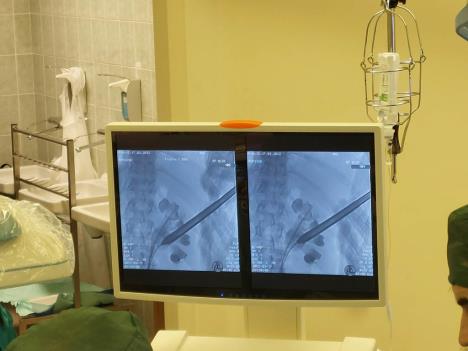

Indikacija za primenu PCNL metode - razbijanja kamena u bubregu perkutanim pristupom je kamen u bubregu 20 mm ili veći (za donji pol bubrega 15mm ili veći) ili ukoliko drugi oblici lečenja nisu dali očekivane rezultate. Minimalnoinvazivni zahvat se sastoji u obezbeđivanju direktnog pristupa kamenu u bubregu kroz punkcioni kanal i kamen se razbija laserskom sondom. PCNL tehnika omogućava da se fragmenti razbijenog kamena lako isperu iz bubrežne šupljine i ima veću stopu uspeha uklanjanja kalkuloze od drugih tehnika. Takođe, odlikuje je znatno manji postoperativni bol i raniji povratak svakodnevnim aktivnostima.